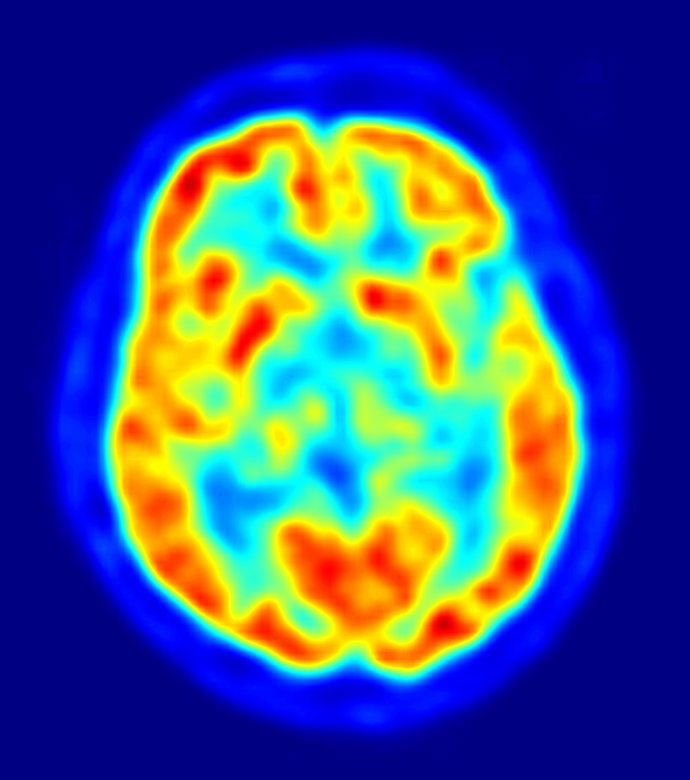

Una parte del cerebro humano funciona como Internet

Un equipo investigador del grupo de Neuropsicología Clínica del Instituto Universitario de Investigación en Ciencias de la Salud (UNICS) de la Universidad de Baleares ha realizado un valioso hallazgo al descubrir que la parte prefrontal del cerebro humano funciona como la red de Internet, pudiendo realizar múltiples y nuevas conexiones neuronales en el caso de que una lesión dañara esa región del cerebro.

El doctor Francisco Barceló, responsable del equipo científico del UNICS, ha liderado la investigación, llevada a cabo de forma conjunta con la Universidad de California (EE.UU.), y que ahora recoge la revista 'Neuron'. Así, el estudio concluye que esa parte del cerebro humano funciona "en red", lo que significa que si a consecuencia de una lesión física esa región sufre daños irreparables los circuitos neuronales se "reconfiguran en cuestión de segundos", estableciendo nuevas conexiones y permitiendo que fluya la información de nuevo.

"Ello no conlleva la reparación del daño, sino que éste se ve compensado gracias a la gran plasticidad de esa parte del cerebro, en la que se encuentra una red flexible y dinámica de interconexiones neuronales", ha explicado el doctor Barceló en declaraciones a Europa Press.

Así, el investigador destaca que la importancia del descubrimiento reside en que durante décadas la parte prefrontal del cerebro fue un "misterio" y se la llegó a considerar "silente". "La comunidad científica llegó a pensar que no tenía ninguna función, debido a que muchos pacientes que habían sufrido lesiones en el córtex prefrontal mostraban una recuperación asombrosa de sus facultades, como si no hubieran sufrido ningún daño", ha relatado.

La explicación, aclara Barceló, se encuentra en la gran "plasticidad neuronal" de esa parte del cerebro, lo que permite superar lesiones gracias a la "continua reconfiguración" de las conexiones neuronales.

La región prefrontal controla la parte más "intrínsecamente humana" del cerebro, relacionada con "la capacidad de comprender el lenguaje hablado, de recordar el pasado o sentir y emocionarnos con esos recuerdos. Afecta a la capacidad de planificar el futuro, o ser animales sociales", detalla el investigador de la UIB.

Esta automática compensación del daño no sucede con la parte occipital (vista) o la parte motora del cerebro, dado que si se produce una lesión en esas regiones el daño es difícilmente reducido.

Así, los investigadores han establecido una comparación entre el cerebro y la red y han concluido que las neuronas se comportan como si navegaran por Internet, quedando probada la gran capacidad para "readaptarse" al nuevo entorno tras una lesión. "La existencia de Internet nos ha ayudado mucho a entender nuestro cerebro", ha concluye el doctor Barceló.